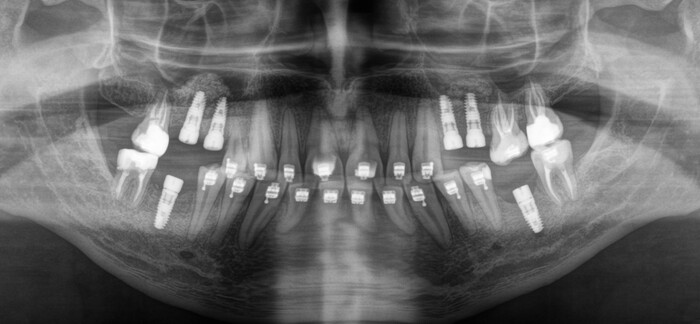

После недолгой беседы и осмотра

Роману было предложено сделать компьютерную томографию для более детальной диагностики и составления комплексного плана лечения.

На снимке видно, что он следил за зубами, занимался лечением, но в определенный момент что-то пошло не так. После проведения совместной консультации со всеми смежными специалистами (ортодонтом, ортопедом, терапевтом) пациенту был предложен комплексный план лечения, который включает в себя:

- удаление остаточных корней зубов, которые не подлежат восстановлению

- лечение и/или перелечивание зубов, которые в этом нуждаются

- ортодонтическое исправление прикуса

- установка имплантатов в процессе брекет-лечения

- временное протезирование на имлантатах

- постоянное протезирование на имплантатах и на жевательных зубах, которые ранее были

пролечены эндодонтически (в которых удалили нервы).

Коронок на рентгеновском снимке вы не увидите, потому что пластик не рентгеноконтрастен. Видны лишь металлические абатменты, за которые «держится» пластмассовая часть, – такие палки-переходники между имплантатом и коронкой. Временные коронки изготовлены из фрезерованной пластмассы. Пластмассовый брусок выпиливается в специальном станке и на выходе представляет собой практически готовую коронку.

В процессе лечения 7-ой зуб на нижней челюсти треснул, появился скол, пришлось от него тоже избавиться. Ниже снимок с постоянными коронками и «внеплановым» имлпантатом:

Коронки на этом снимке уже четко различимы, потому что сделаны из керамики.